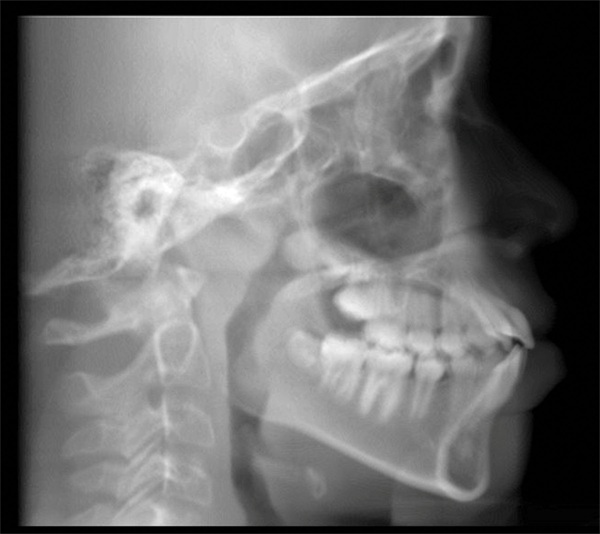

The pretreatment lateral cephalometric radiograph supported the clinical impression of bimaxillary dentoalveolar protrusion (Fig. 3). Both the maxillary and mandibular incisors were protrusive and proclined, contributing to the soft-tissue imbalance. The cephalometric picture matched the clinical one: prominent incisors, protrusive lips, lip incompetence, and mentalis strain.

Fig. 3